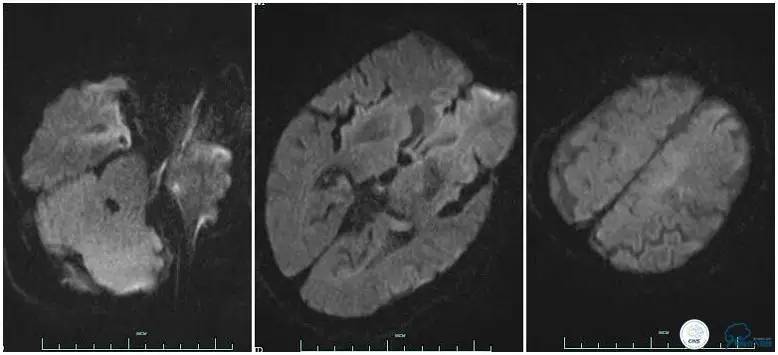

术后头颅CT复查。

术后复查头颅CTA。

术后复查头颅MRI。

术后第二天患者意识清,言语清,右上肢肌力1级,右下肢肌力3级,左上肢肌力5级,左下肢3级。

术后90天随访右上肢肌力3级,左上肢肌力5级,双下肢肌力4级,mRS评分3分。

3.该患者治疗过程中存在一定不足,患者右侧肢体偏瘫症状明显,取栓过程中因血管扭曲未能优先处理左侧大脑前动脉。虽然术后血流完全再通,但复查头颅MRI左侧大脑前供血区域仍有大片梗死,右侧上肢肌力恢复不理想。